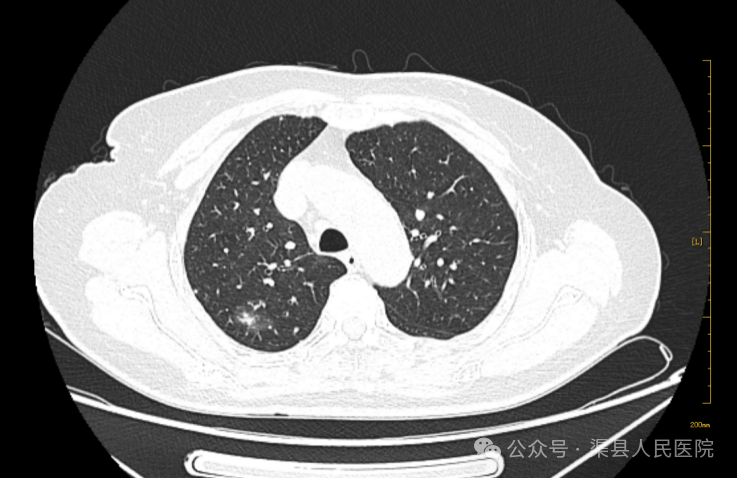

近日,我院胸外科接诊了一位患者,因检查发现肺结节入院。胸部CT发现右肺上叶后段结节。(如下图)

进一步完善胸部增强CT,右肺上叶后段(IM65)实性结节,大小约为14mm×8mm,增强扫描轻度强化。(如下图)